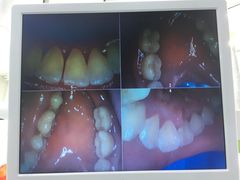

• 牙博士口腔品牌连锁(杨浦店)

• -牙博士口腔品牌连锁(杨浦店)

敏敏 | 21-08-20